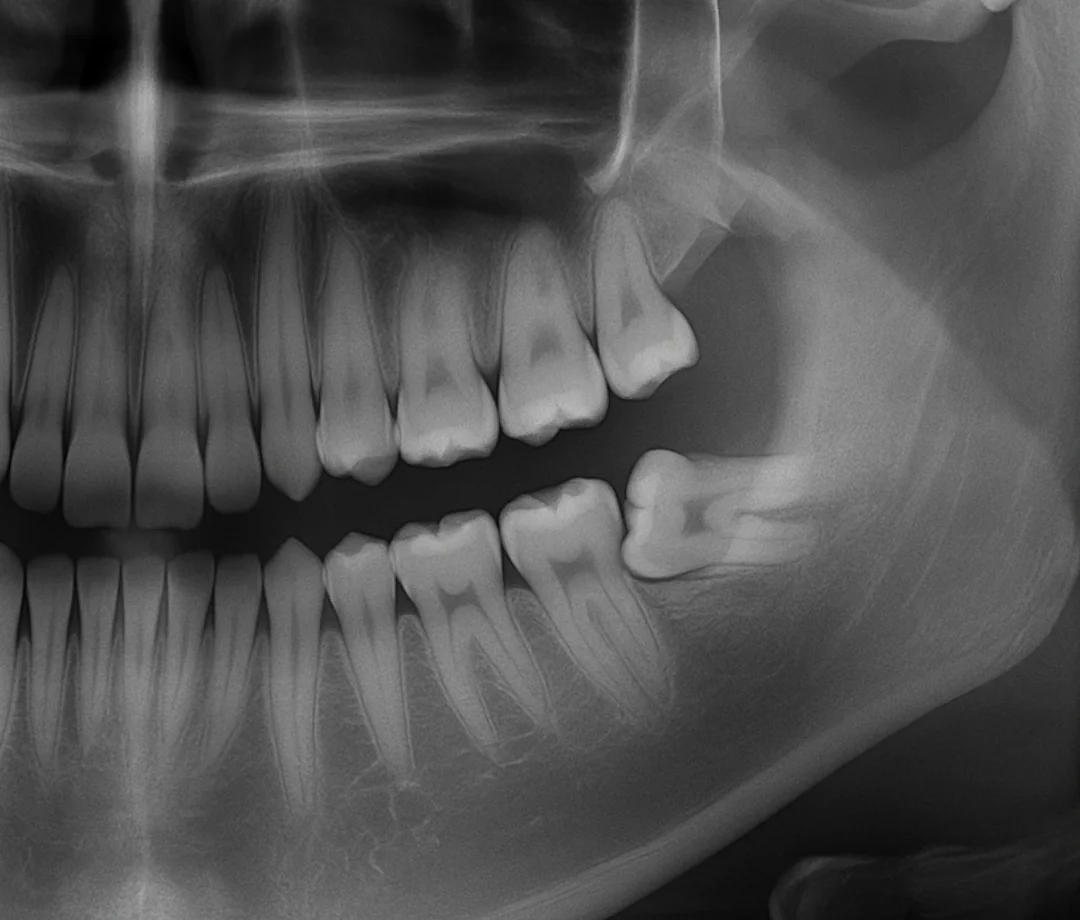

Si, realizamos radiografías panorámicas